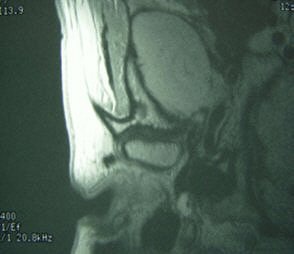

![]() |

Fifty-year-old woman with clicking and pain in both TMJs, 8-mm mandibular advancement, and MIO that decreased from 42 mm to 40 mm postoperative. Above, bilateral, right anterior disk displacement on MRI preoperative, which did not change on postoperative MRI, below. Images courtesy of Dr. Jessica Lee.